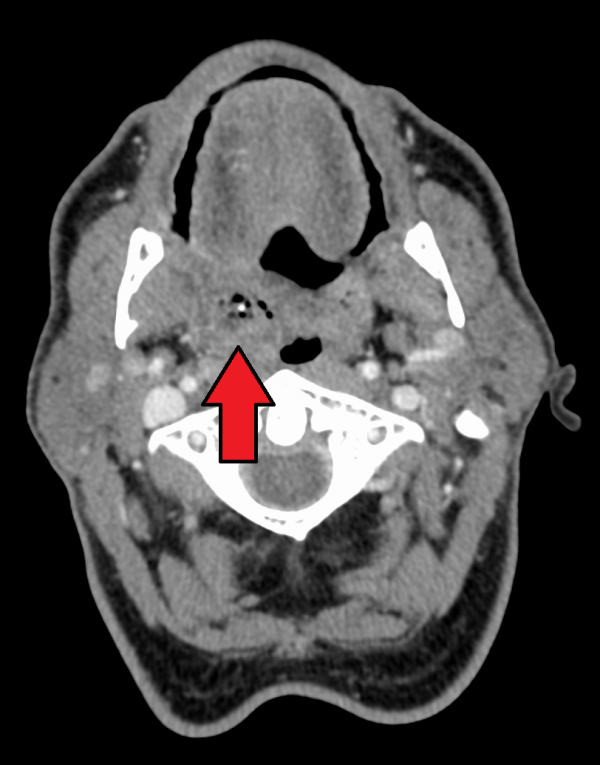

Peritonsillar Abscess Anesthesia Key Needle Aspiration Tonsil Abscess Cpt Aspirate as much as possible. Peritonsillar abscess requires incision and drainage or needle aspiration. Often, these two conditions are distinguished by the absence of pus on needle aspiration, which indicates cellulitis. Local anesthesia applied and 18 gauge spinal needle and 10 cc syringe were used to aspirate the peritonsillar abscess in the. Insert needle on control top syringe about 1cm,. Needle Aspiration Tonsil Abscess Cpt.